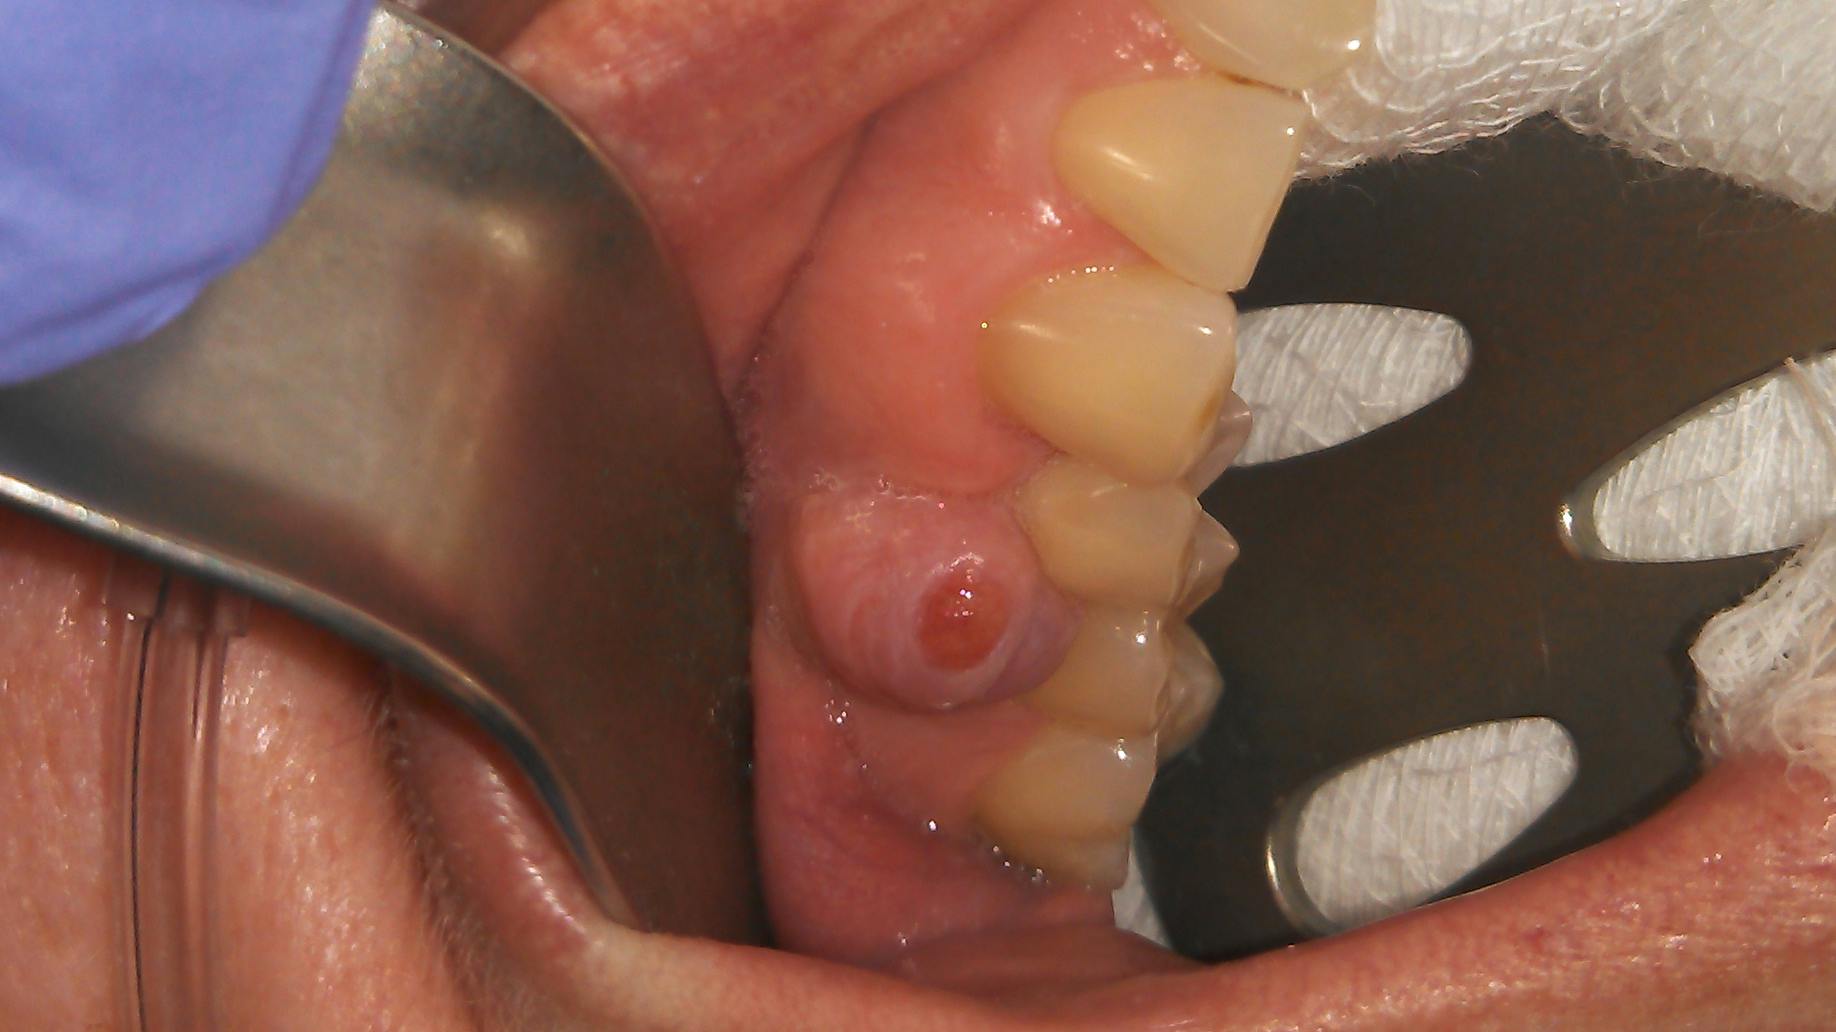

Clinical assessment on the lower lip revealed:

- 7 mm-plus soft, exophytic, dome-like lesion

- Normal lip color

- Fluid filled with a slightly red base

- No pain, but the patient was having a hard time eating due to position and size of lesion